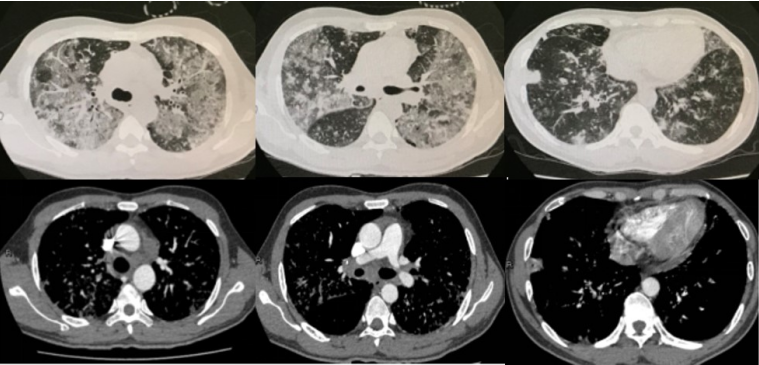

图4 右下后叶基底段开口黏膜活检结果:镜检为低分化腺癌,免疫组化:CK7(+),TIF-1(+),NapsinA(+),CK5/6(+),P63(-),P40(-),Cgd(-),Syn(-),CD56(-),ALK(D5F3)(+),ALK-N(-),符合低分化腺癌12月14日起,患者气促开始好转,咳嗽、咳痰减轻,复查胸片可见肺部吸收改善,12月16日胸片明显好转(图5),氧合指数升至203 mmHg,逐步减低Airvo支持参数,12月18日患者气促基本缓解,查血气提示氧合指数484 mmHg,改为鼻导管吸氧,复查胸部CT提示双肺病变明显减轻(图6),12月19日患者体温稳定,感染指标及胸片好转,亚胺培南降阶梯为哌拉西林他唑巴坦钠4.5g q8h联合替考拉宁抗感染治疗,12月20日患者无明显咳嗽、咳痰及气促,好转步行出院。

图5 自左至右分别为2017年12月13日、15日、16日及17日胸片